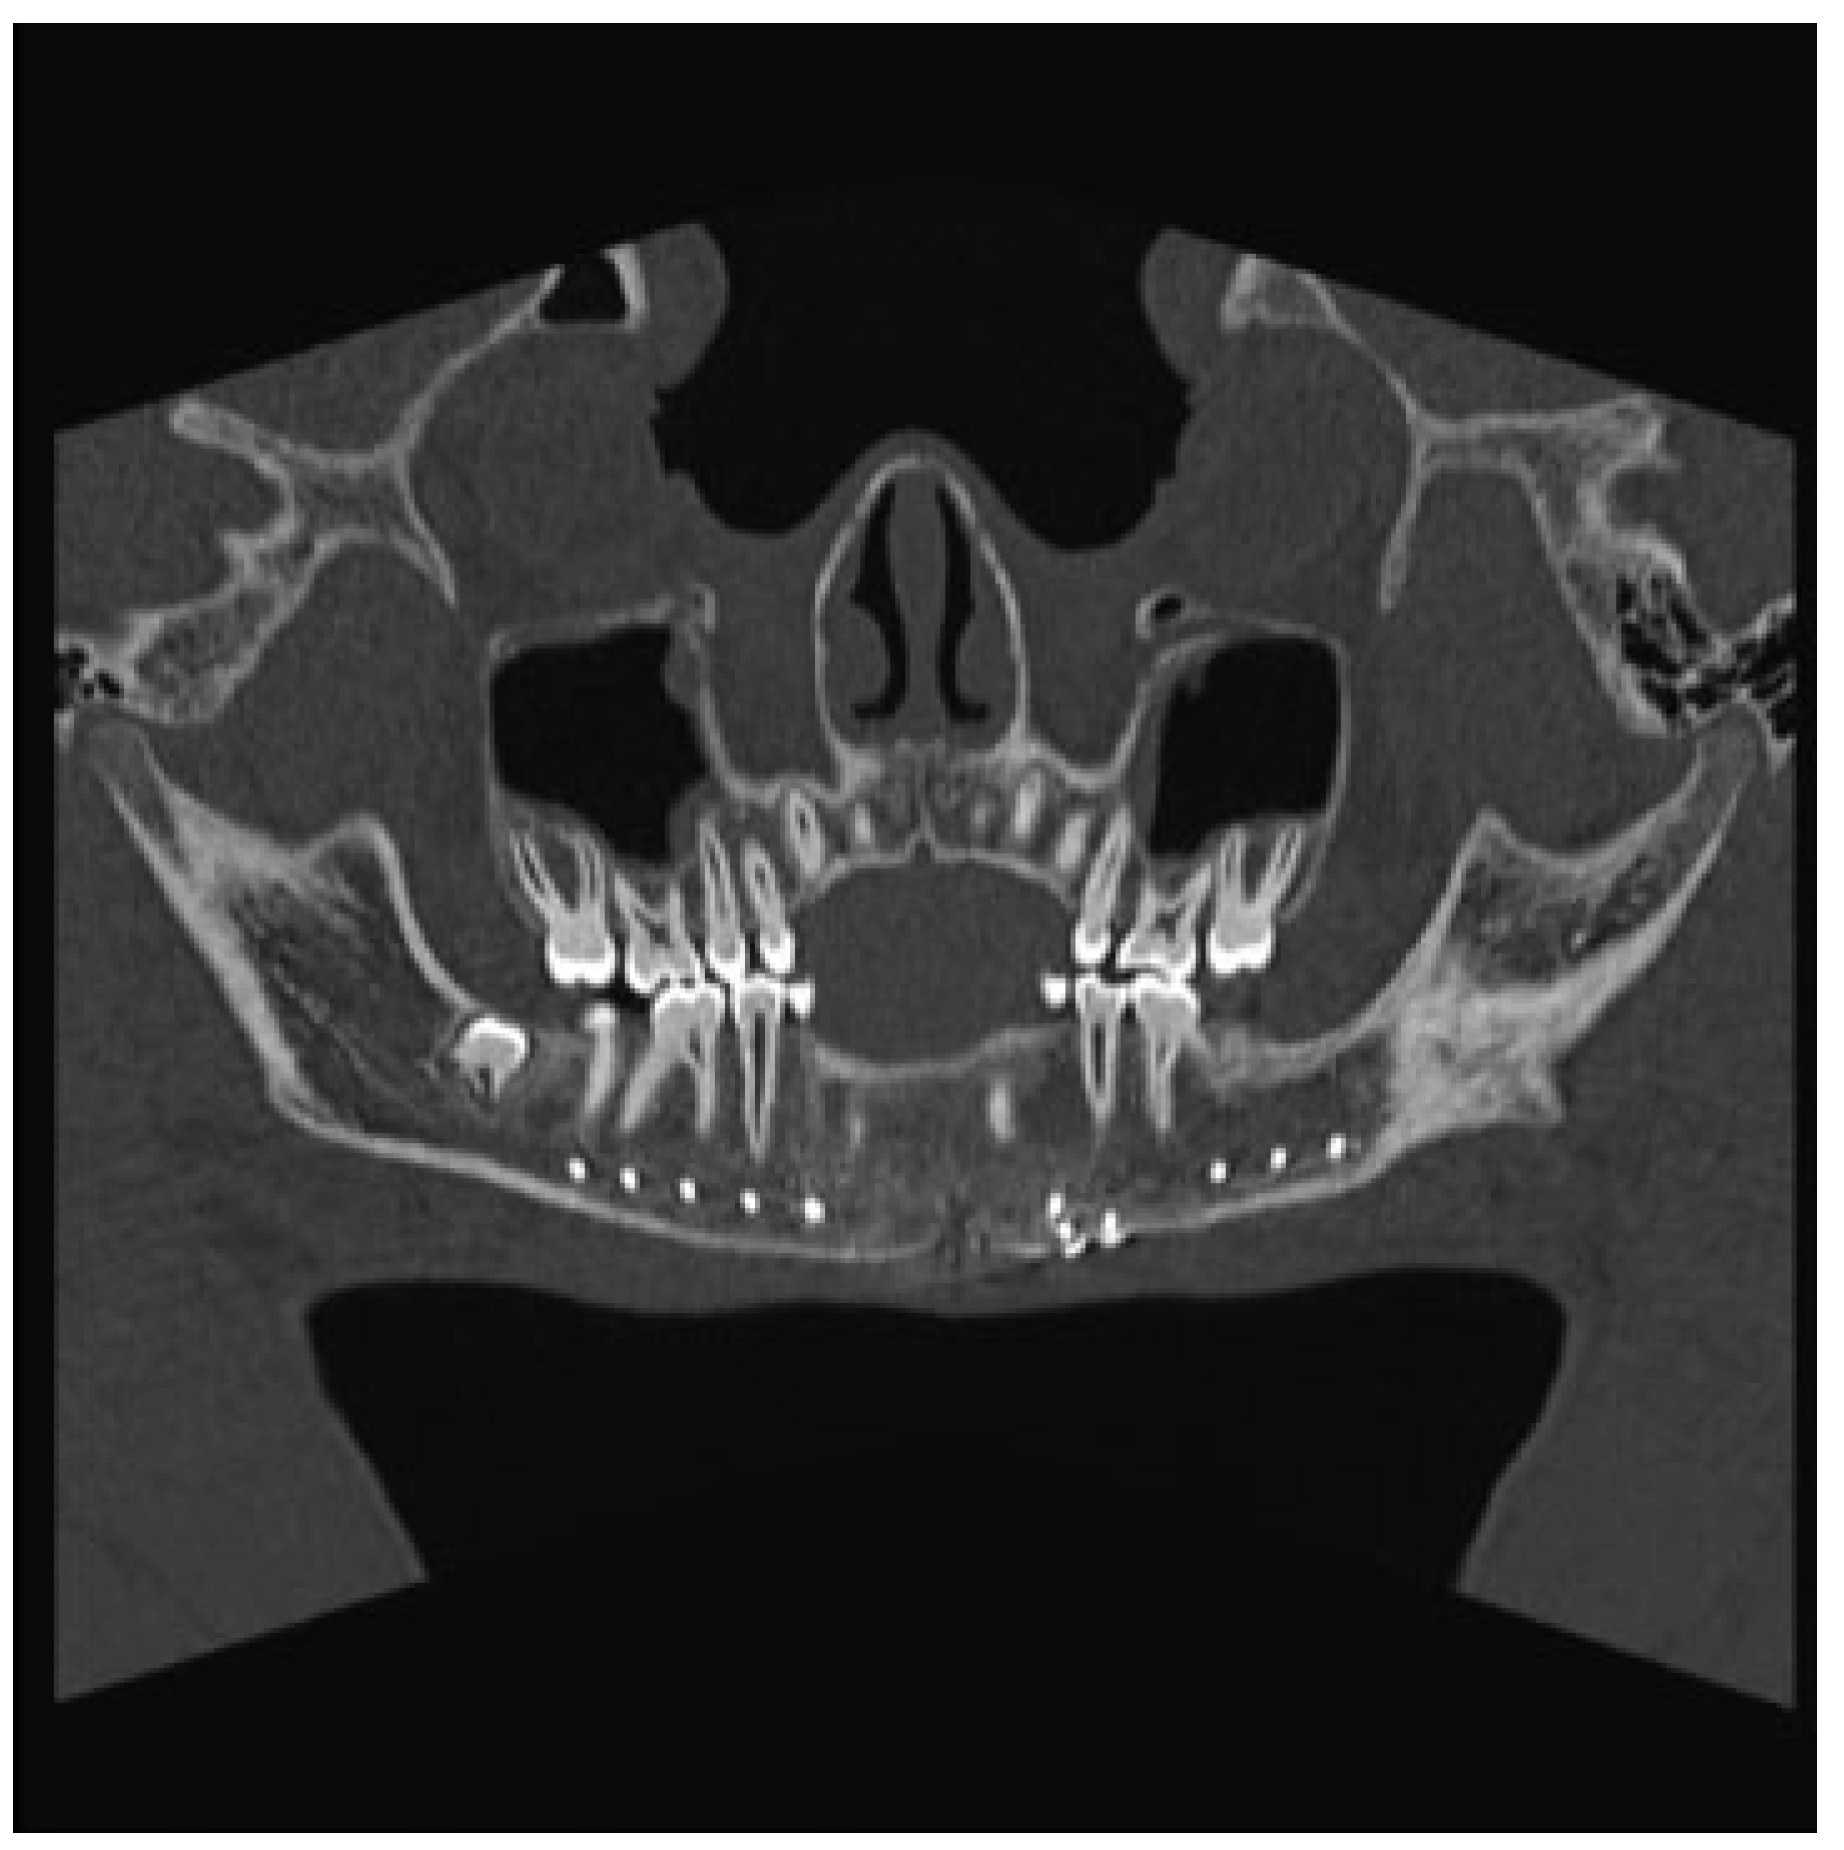

Figure 6.

Panorex computed tomography scan obtained 1 year postoperatively demonstrating near-complete ossification of the cys- tic defect of the mandible.

The patient was taken to the operating room the next day. With evidence of a lesion in the mandible of unknown pathology, the decision was made to proceed with a trans- cervical approach to provide broader access that would allow for adequate curettage and resection if needed. The fracture line and cystic cavity were identified. A cystic lumen was filled with organized blood clotlike material. No definitive solid tissue was identified (Figure 2). The clot and the cortex of the cavity were curetted and sent for histologic interpreta- tion. Occlusion had been established previously with max-illomandibular fixation. The mandibular fracture was reduced and repaired with a lower-border Synthes Matrix mandibular locking bar with bicortical screws (Synthes CMF, West Chester, PA, USA). An additional 2.0 Synthes Matrix mono- cortical plate was used to secure a sizable secondary fragment of the cystic wall (Figure 3). The cystic space was packed with Gelfoam (Pfizer, Pharmacia and Upjohn Company, Kalamazoo, MI, USA), as a means of filling the cystic dead space with a nonpermanent material that would not interfere with later osteogenesis. The remainder of surgery was uncomplicated and a small suction drain was placed at closing. A postoperative image revealed satisfactory alignment (Figure 4). The drain was removed on postoperative day 2, and the patient was dis-charged home 3 days later, tolerating a soft diet. Fifteen days after discharge, the patient returned to our ED with worsening pain and swelling at the surgical site. He was diagnosed with a small submental abscess. The patient was admitted and treated successfully with bedside incision and drainage and a short course of intravenous antibiotics. The remainder of his recovery was uneventful, with good occlusion and function. Follow-up CT imaging at 6 weeks showed good fracture healing and some early osteogenesis within the cystic cavity (Figure 5). One year after surgery, he had normal occlusion and no evidence of hardware complications. Additionally, CT imaging demonstrated ossification of the majority of the cystic space, with only a few small lateral areas of persistent cyst (Figure 6).